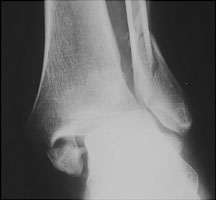

- Click on the image for a larger versionAAP radiograph of the ankle. This demonstrates fractures of both the medial and lateral malleoli.